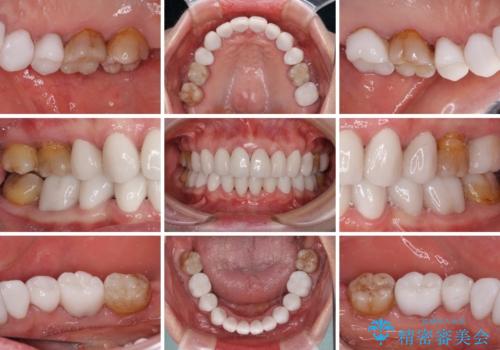

歯の色はホワイトニングかセラミッククラウンで対応することとしましたが、ブラックトライアングルが目立つことが予想されたため、目立つ範囲をオールセラミッククラウンで補綴することとしました。

矯正治療をせず、セラミッククラウンので口元の突出感を改善しようとしても、神経を取り除く必要があったり、口元の突出感はあまり改善されなかったりと、後悔する可能性が高くなります。